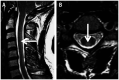

Recent findings: Neurologic complications related to bariatric surgery are predominantly due to nutrient deficiencies. Common early complications include Wernicke encephalopathy due to thiamine deficiency, and late complications include myelopathy or myeloneuropathy due to vitamin B12 or copper deficiency.